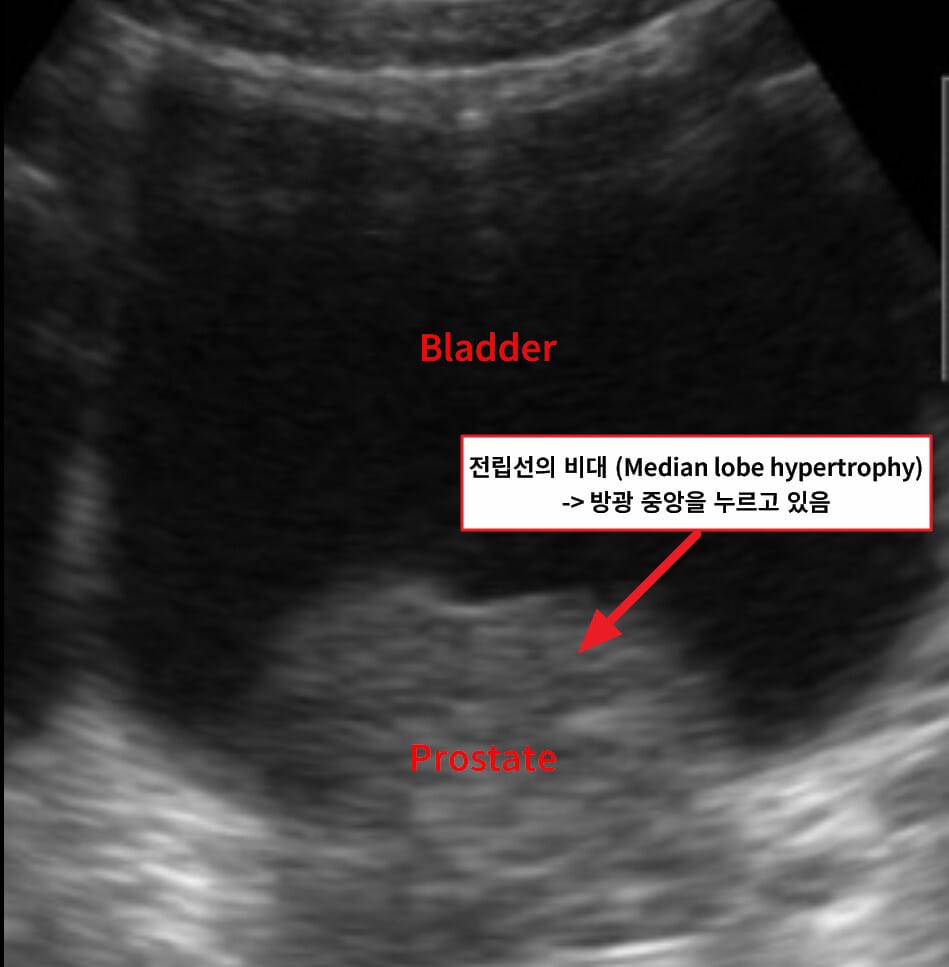

| 🔵 전립선 초음파 |

| 용적 ≥30 mL이면 비대증 진단 가능 |

초음파 및 MRI에서 전립선 용적 증가와 중간엽(transition zone) 비대가 특징적입니다.

| 🔍 특징적 영상소견 요약 |

| ✅ 전립선 용적 증가 (≥30 mL) |

| 경직장 초음파에서 비대 확인 |

| ✅ 중심부 압박 및 요도 협착 |

| 중앙 요도를 압박하며 narrowing 보임 |

| ✅ 방광 잔뇨량 증가 |

| 비대에 의한 배출 장애로 잔뇨 발생 |